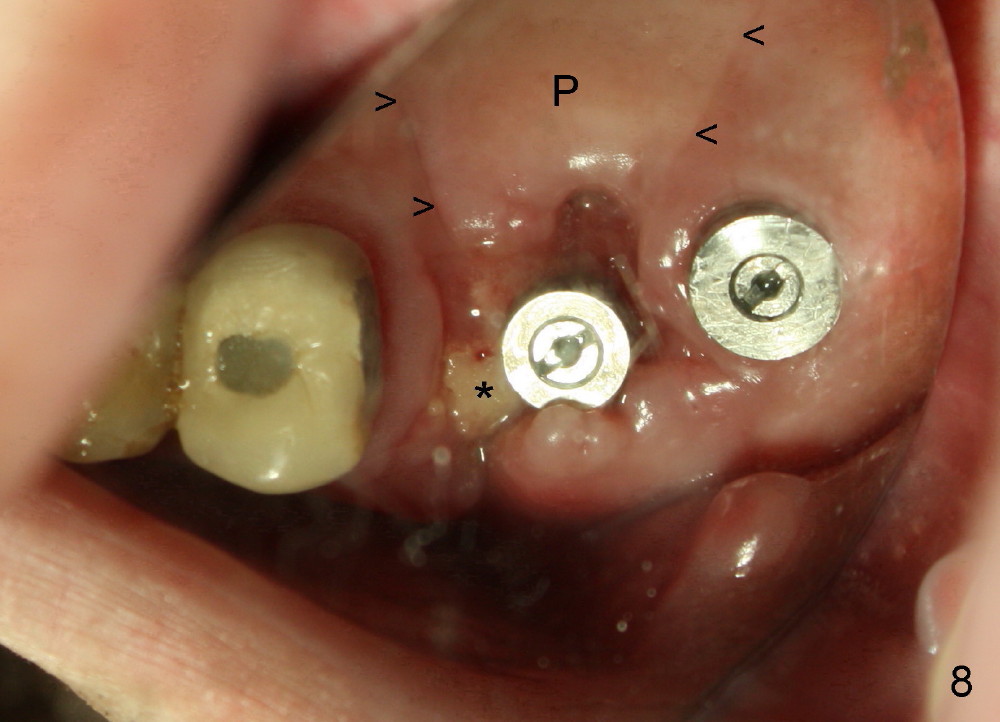

In spite of releasing buccal and palatal (P) flaps with suturing (Fig.8,9 small arrowheads), the palatal socket is exposed 2 weeks postop (big arrowhead and ). The mesiobuccal bone is also exposed (Fig.8 *). The patient reports bleeding and pain immediately postop. Both can be prevented if a large healing abutment is used (8 or 9 mm in diameter) or an immediate provisional is fabricated.